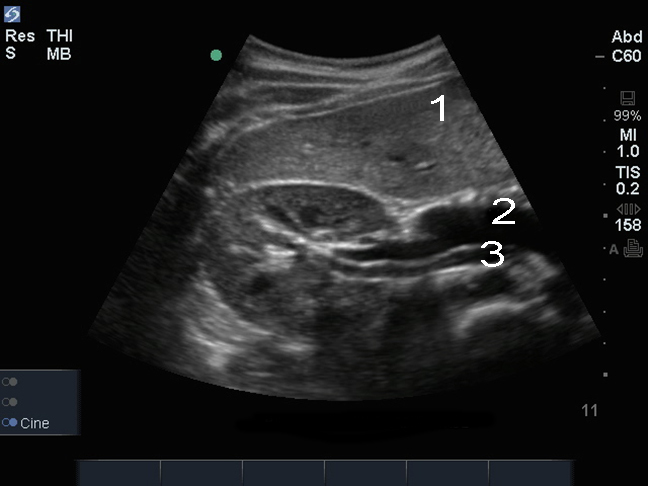

Bild: Leber und rechte Niere, transversal

Leber

Vene

Arterie